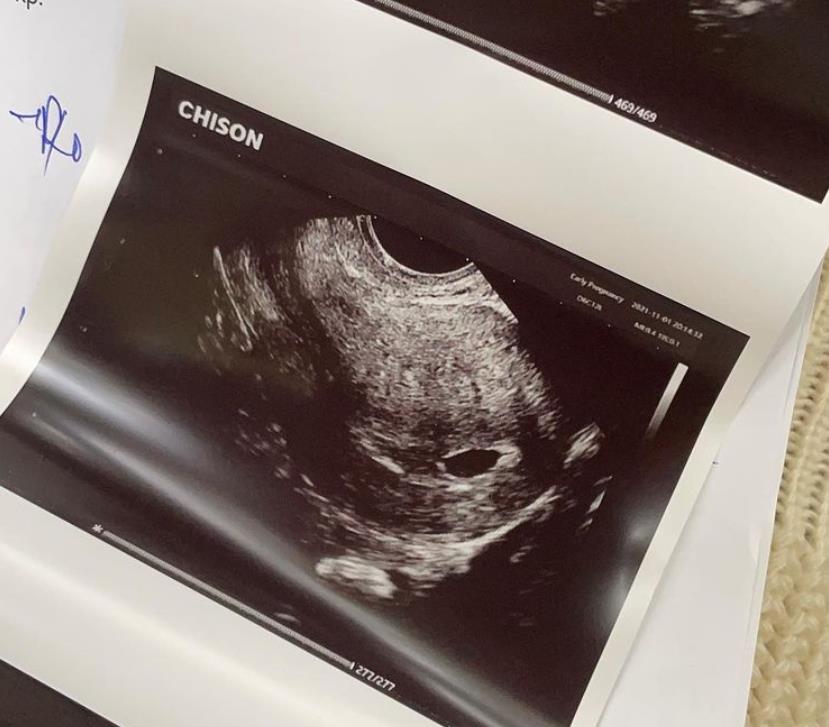

Luis Gabriel și Haziran sunt în culmea fericirii! Iubita manelistului este însărcinată în 6 săpătmâni și a dat vestea cea mare în urmă cu puțin timp. Vedeta a postat o fotografie pe pagina ei de Instagram, în care apare ecografia sarcinii. Cântăreața a dezvăluit că este cea mai frumoasă veste pe care a primit-o vreodată și este foarte entuziasmată să devină mamă.

„Baby loading .. ❤️👶🏼 6 weeks 🙏 Suntem cei mai fericiți oameni de pe pământ! Cea mai frumoasă veste pe care am primit-o!”, a scris Haziran în descrierea fotografiei.